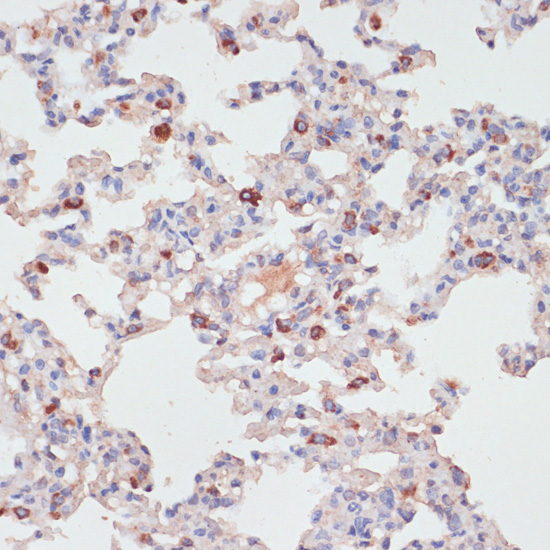

Immunohistochemistry of paraffin-embedded rat lung using PKC?? antibody at dilution of 1:100 .